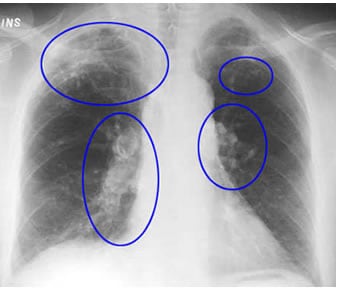

Tale procedimento non ha sicuramente favorito la conservazione dei polmoni stessi, ridotti dopo millenni ad una poltiglia densa difficilmente studiabile. Al di là delle evidenze di tubercolosi emerse dagli scheletri pervenutici (vedi https://laciviltaegizia.org/2023/01/21/virus-e-batteri/) anche il buon Ruffer, che abbiamo conosciuto come uno dei massimi esperti nello studio delle mummie all’inizio del XX secolo, trovò infatti una marea di difficoltà a fornire informazioni affidabili. Credette di aver ritrovato tracce di polmonite, ma tale interpretazione è ancora molto discussa.

In anni più recenti è stato invece possibile identificare con relativa certezza i segni di silicosi dovuta alla sabbia ed alla polvere di roccia, frequente negli scalpellini ancora oggi, e di antracosi dovuta all’inalazione del fumo di carbone – probabilmente frequente nei lavoratori delle necropoli o comunque dovuta ai fuochi mantenuti accesi nei luoghi chiusi – oltre a tracce molecolari di diversi virus respiratori. In epoca Covid qualche studioso aveva proposto anche di studiare i coronavirus rintracciati nelle mummie egizie per studiarne l’evoluzione.